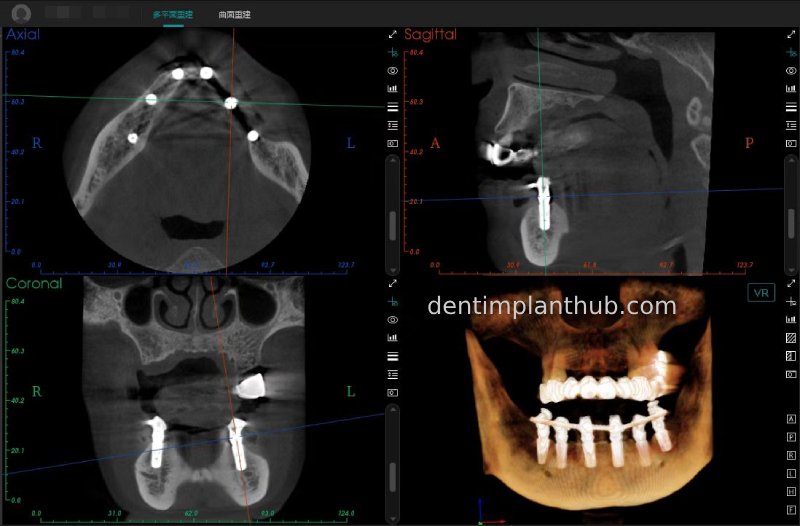

A review of the CBCT on 6/10/23 was more promising and a surgical plan was subsequently drawn up.

CBCT review results on 13 May '24

46

44

42

32

34

36